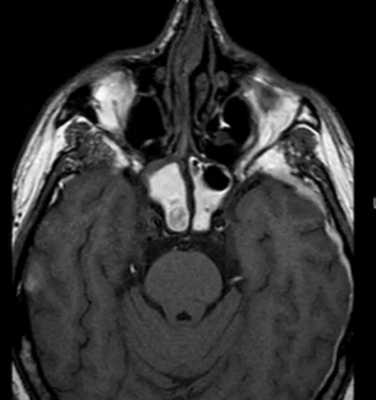

![Гемосинус на МР-снимке головы]()

Гемосинус на МР-снимке головы